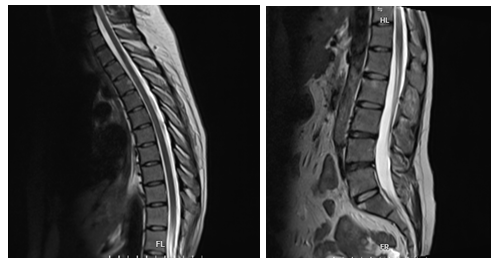

Hình ảnh chụp cộng hưởng từ cột sống ngực và cột sống lưng của người bệnh

Người bệnh được chỉ định chụp cộng hưởng từ (MRI) cột sống lưng, cột sống ngực và khớp cùng chậu, xét nghiệm cho thấy người bệnh mang kháng nguyên HLA-B27 dương tính. Người bệnh được chẩn đoán: Viêm cột sống dính khớp, một bệnh tự miễn mạn tính thuộc nhóm bệnh lý cột sống – khớp có thể gây biến dạng, dính khớp, tàn phế nặng nếu không được điều trị kịp thời và đúng cách.